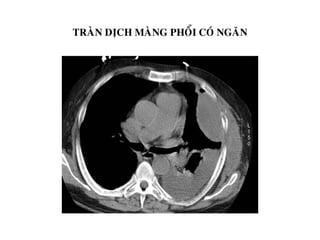

TRAØN DÒCH MAØNG PHOÅI COÙ NGAÊN

Traøn dòch maøng phoåi töï do: dòch töï do

khoang maøng phoåi, eùp gaây xeïp phoåi

thuï ñoäng

Traøn muû maøng phoåi khu truù: dòch khu

truù ôû caùc tuùi maøng phoåi dính nhau,

taêng quang caùc thaønh tuùi naøy sau tieâm

caûn quang